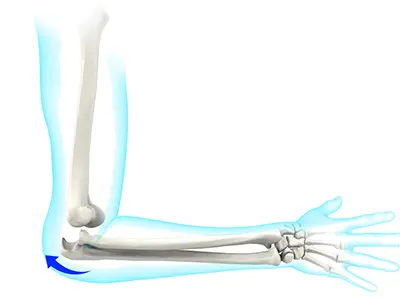

Elbow Stiffness

Elbow stiffness is a condition characterized by a restricted range of motion of the elbow causing difficulty bending, straightening, or rotating your arm.

Elbow Contracture

Elbow contracture refers to a stiff elbow with a limited range of motion. It is a common complication following elbow surgery, fractures, dislocations, and burns.